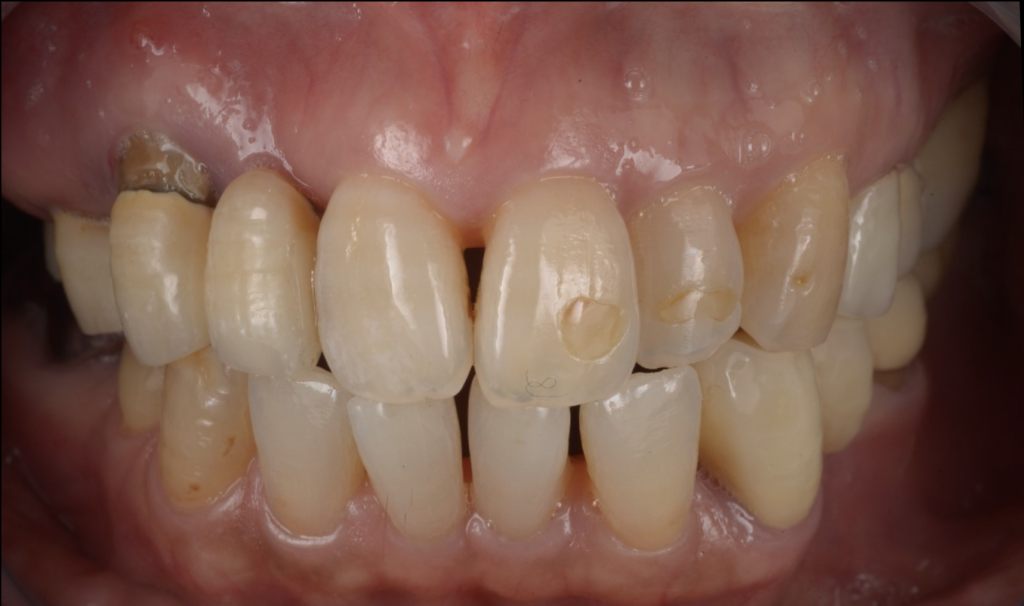

今回ご紹介するのは、噛み合わせに無理がある補綴設計が背景となり、腫れ・動揺が進行して日常の食事にも支障が出ていた患者様のケースです。

なぜ「膿む・グラグラする」「噛めない」まで進んだのか

歯が腫れたり動いたりする原因はさまざまですが、再治療で重要なのは

“なぜ壊れたのか”を力のかかり方から見直すことです。

補綴設計や噛み合わせに無理があると、特定の部位に負担が集中し、

- 炎症(腫れ・排膿)

- 動揺(グラつき)

- 噛むと痛い/噛めないといった状態に進行することがあります。

奥歯が噛めないと、前歯が“代わりに噛む”ようになってしまう

奥歯で噛めない状態が続くと、無意識に前方で噛もうとして

切端咬合(前歯同士がぶつかる噛み方)になっているケースがあります。